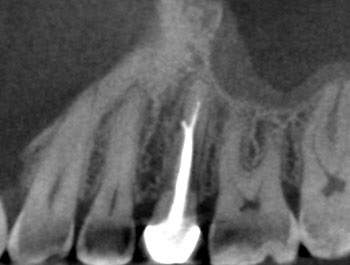

Case 1:A J-shaped lesion

Tooth #30 had a diagnosis of previous root canal treatment with symptomatic apical periodontitis. The mesial root had a classic J-shaped radiographic lesion and a narrow probing defect from the buccal furcation to the root apex. No crack could be seen on what little root surface was visible. The likelihood of VRF, or the possibility of a failing root canal with a chronic apical abscess, were discussed. The latter could be treatable. The plan was to attempt re-treatment after internal inspection for a possible VRF.

Fig. 1: Preoperative PA.

Fig. 2: Postoperative PA.